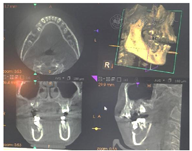

患者,女性,11岁,2018年3月以"右下后牙区囊肿及右上后牙残根2月余"为主诉就诊。患者约2年前治疗口内多颗坏牙,45行根管治疗,16行充填治疗,治疗后未定期复查,16牙冠逐渐脱落,于外院拍片检查发现16残根,右下后牙区囊肿。患者既往体检,无全身病史,父母均健康,无类似病史。检查见:16残根,近远中边缘深达龈下2~3 mm,颊舌边缘位于龈上1.0~1.5 mm,大量腐质。15,17未萌出,46和44之间间隙约2 mm(图1)。曲面断层片显示:16残根,根尖区见低密度影,15阻生,牙根发育Nolla 8期,17牙根发育Nolla 7期,18牙根发育Nolla 5期(图2)。44-46颊侧牙槽骨膨隆,质地硬,无压痛,未及波动感,85远中及牙合面大面积充填体,边缘欠密合,不松动。曲面断层片显示:85牙根大部分吸收,远中根剩余约1mm,根管内见根充影像,45牙轴偏向远中,牙根发育Nolla 8期,44远中至46近中范围可见大面积低密度影,边缘清晰,包绕于45牙颈部。CBCT显示:低密度影近卵圆形,大小约为1.0 cm×1.2 cm×1.4 mm,边界清楚,颊侧骨板薄(图3)。